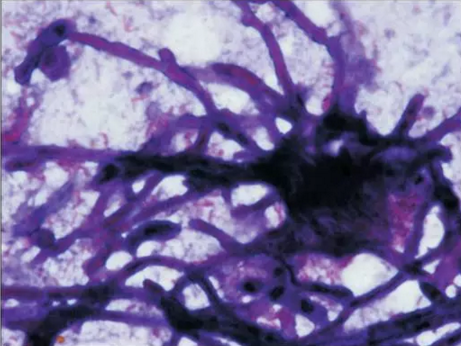

初步診斷為口腔毛霉菌病。取部分軟腭組織做病理學(xué)檢查。病理檢查顯示組織中含有大量無包膜的真菌、壞死血管組織,結(jié)果支持毛霉菌病的診斷。

3.png